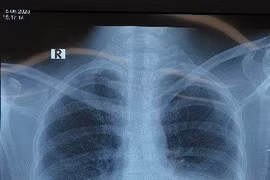

Ho khan suốt 1 tháng, kèm theo hàng loạt triệu chứng như khó thở, đau âm ỉ ngực phải, hụt hơi, ông N.K.T. 62 tuổi, (Hà Nội) quyết định đến viện bất ngờ phát hiện tràn dịch màng phổi do ung thư di căn.